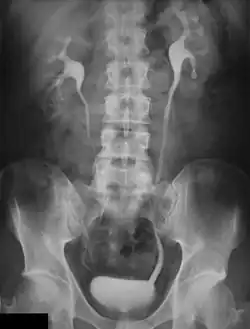

An intravenous urography (IVU), also called an intravenous urogram or simply urogram, is a radiological procedure used to visualize abnormalities of the urinary system, including the kidneys, ureters, and bladder. Unlike a kidneys, ureters, and bladder x-ray (KUB), which is a plain (that is, noncontrast) radiograph, an IVP uses contrast to highlight the urinary tract.

An injection of X-ray contrast medium is given to a patient via a needle or cannula into the vein,[7] typically in the antecubital fossa of the arm. The contrast is excreted or removed from the bloodstream via the kidneys, and the contrast media becomes visible on X-rays almost immediately after injection. X-rays are taken at specific time intervals to capture the contrast as it travels through the different parts of the urinary system.[7] At the end of the test, a person is asked to pass urine and a final X-ray is taken.[7]

Immediately after the contrast is administered, it appears on an X-ray as a 'renal blush'. This is the contrast being filtered through the cortex. At an interval of 3 minutes, the renal blush is still evident (to a lesser extent) but the calyces and renal pelvis are now visible. At 9 to 13 minutes the contrast begins to empty into the ureters and travel to the bladder which has now begun to fill. To visualize the bladder correctly, a post micturition X-ray is taken, so that the bulk of the contrast (which can mask a pathology) is emptied.